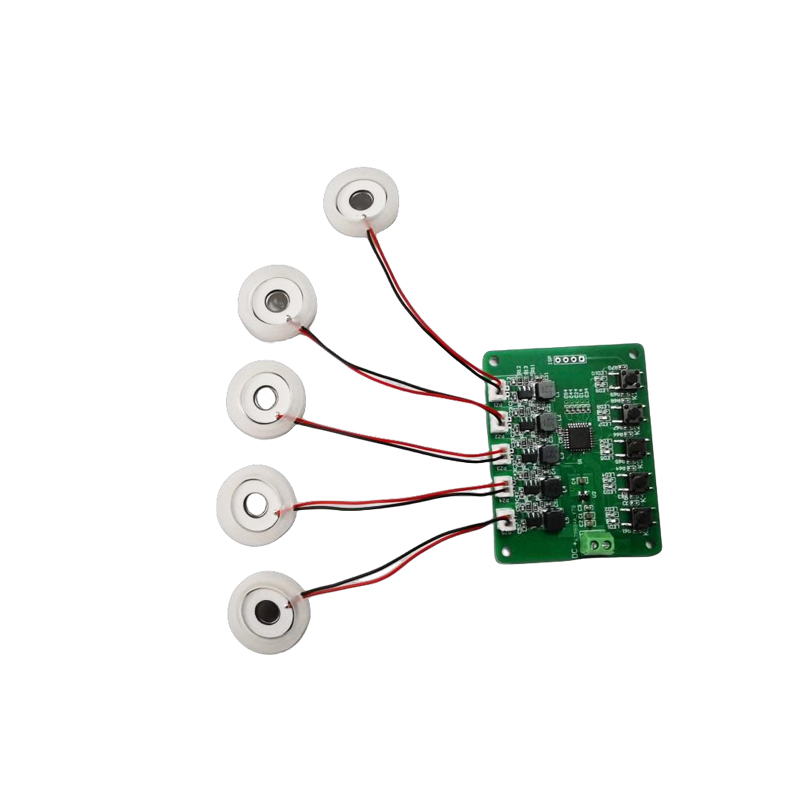

Medyczne tabletki do nebulizatora siatkowego to precyzyjne elementy stosowane w urządzeniach medycznych do przekształcania leków lub roztworów w drobne cząsteczki aerozolu w celu leczenia różnych chorób układu oddechowego, takich jak astma i przewlekła obturacyjna choroba płuc (POChP) itp., poprzez inhalację. Konstrukcja i dobór materiału arkusza nebulizatora mają kluczowe znaczenie dla zapewnienia skutecznego podawania leku i komfortu pacjenta. Arkusz membrany ze stali nierdzewnej jest dziurkowany w blasze stalowej tysiącami drobnych otworów o oczkach 2-3 μm za pomocą technologii wiercenia laserowego w precyzyjnym procesie laserowym, a następnie jest ściśle połączony z okrągłym arkuszem ceramicznym piezoelektrycznym, który przekształca częstotliwość rezonansową arkusza piezoelektrycznego w energię wibracji o wysokiej częstotliwości poprzez sygnał wyjściowy płytki sterownika PCB i szybko rozkłada płynny lek na drobne cząsteczki aerozolu. Krople te nazywane są również medianą wielkości cząstek. Gdy mediana wielkości cząstek D50 osiąga >60% lub więcej, cząstki będą wystarczająco małe, aby podczas oddychania móc dotrzeć głęboko do płuc do powierzchni pęcherzyków płucnych, poprawiając w ten sposób skuteczność wchłaniania leku i efekt terapeutyczny. Arkusz nebulizatora z mikrosiatką medyczną ma głównie kilka form, arkusz nebulizatora z mikrosiatką ze stali nierdzewnej, arkusz nebulizatora medycznego z niklowo-palladem, arkusz nebulizatora medycznego z polimeru PI i tak dalej. Wszystko powyższe odbywa się poprzez piezoelektryczną konwersję energii wibracji ceramicznych w celu osiągnięcia efektu atomizacji.

Rozpylacz ultradźwiękowy to urządzenie wykorzystujące zasadę wibracji ultradźwiękowych (konwersji energii) do zamiany cieczy na drobne kropelki. Zasadą działania są unikalne właściwości piezoelektryczne ceramiki piezoelektrycznej. Element atomizujący odbierający odpowiednie wzbudzenie sygnału pola elektrycznego wytworzy odpowiednią częstotliwość oscylacji, poprzez rolę wibracji o wysokiej częstotliwości kawitacji cieczy wyrzucanej z powierzchni wody w celu wytworzenia rodzaju cząstek mgły wodnej, atomizowanych dużą liczbą jonów ujemnych i małych cząstek cząsteczek, może osiągnąć wzrost wilgotności otoczenia, rolę świeżego powietrza. Powierzchnia atomizera jest pokryta emalią szklistą o wysokiej temperaturze 800 stopni, aby chronić srebrne elektrody arkusza piezoelektrycznego, zwiększyć odporność atomizera na kwasy i zasady oraz odporność na utlenianie, a także zwiększyć żywotność atomizera. Szeroko stosowany w nawilżaczach wewnętrznych, oczyszczaczach powietrza, leczeniu nebulizatorami medycznymi i samochodach kosmetycznych, e i innych dziedzinach, ale nadaje się również do magazynów, fabryk, nawilżania, dezynfekcji, aby stworzyć atmosferę sprzętu nawilżającego. Tabletki zamgławiające stosuje się głównie w nawilżaniu przemysłowym, zamgławianiu medycznym, zamgławianiu aromaterapeutycznym, nawilżaniu środowiska, zamgławianiu ogrodu i innych scenach.